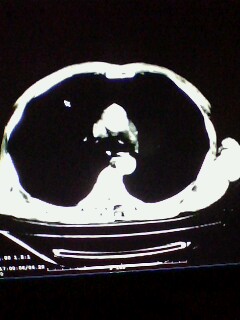

标题: CT28315:咳嗽咳痰咯血半月并胸痛 [打印本页]

标题: CT28315:咳嗽咳痰咯血半月并胸痛

1、纵膈窗效果不好,初步考虑左肺下叶感染性病灶,建议正规抗炎治疗后复查   2、右肺下叶陈旧性病灶伴局部胸膜增厚。

左下肺肿块影,深分叶,考虑肺癌。

考虑左肺下叶周围型肺癌并阻塞性肺炎。